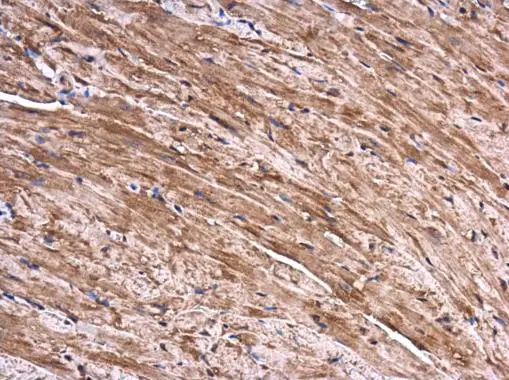

![SEC3 antibody [C2C3], C-term detects SEC3 protein at cytoplasm in mouse heart by immunohistochemical analysis. Sample: Paraffin-embedded mouse heart. SEC3 antibody [C2C3], C-term (GTX119659) diluted at 1:500.

Antigen Retrieval: Citrate buffer, pH 6.0, 15 min SEC3 antibody [C2C3], C-term detects SEC3 protein at cytoplasm in mouse heart by immunohistochemical analysis. Sample: Paraffin-embedded mouse heart. SEC3 antibody [C2C3], C-term (GTX119659) diluted at 1:500.

Antigen Retrieval: Citrate buffer, pH 6.0, 15 min](https://www.genetex.com/upload/website/prouct_img/normal/GTX119659/GTX119659_40338_20160816_IHC-P_M_w_23060519_657.webp)